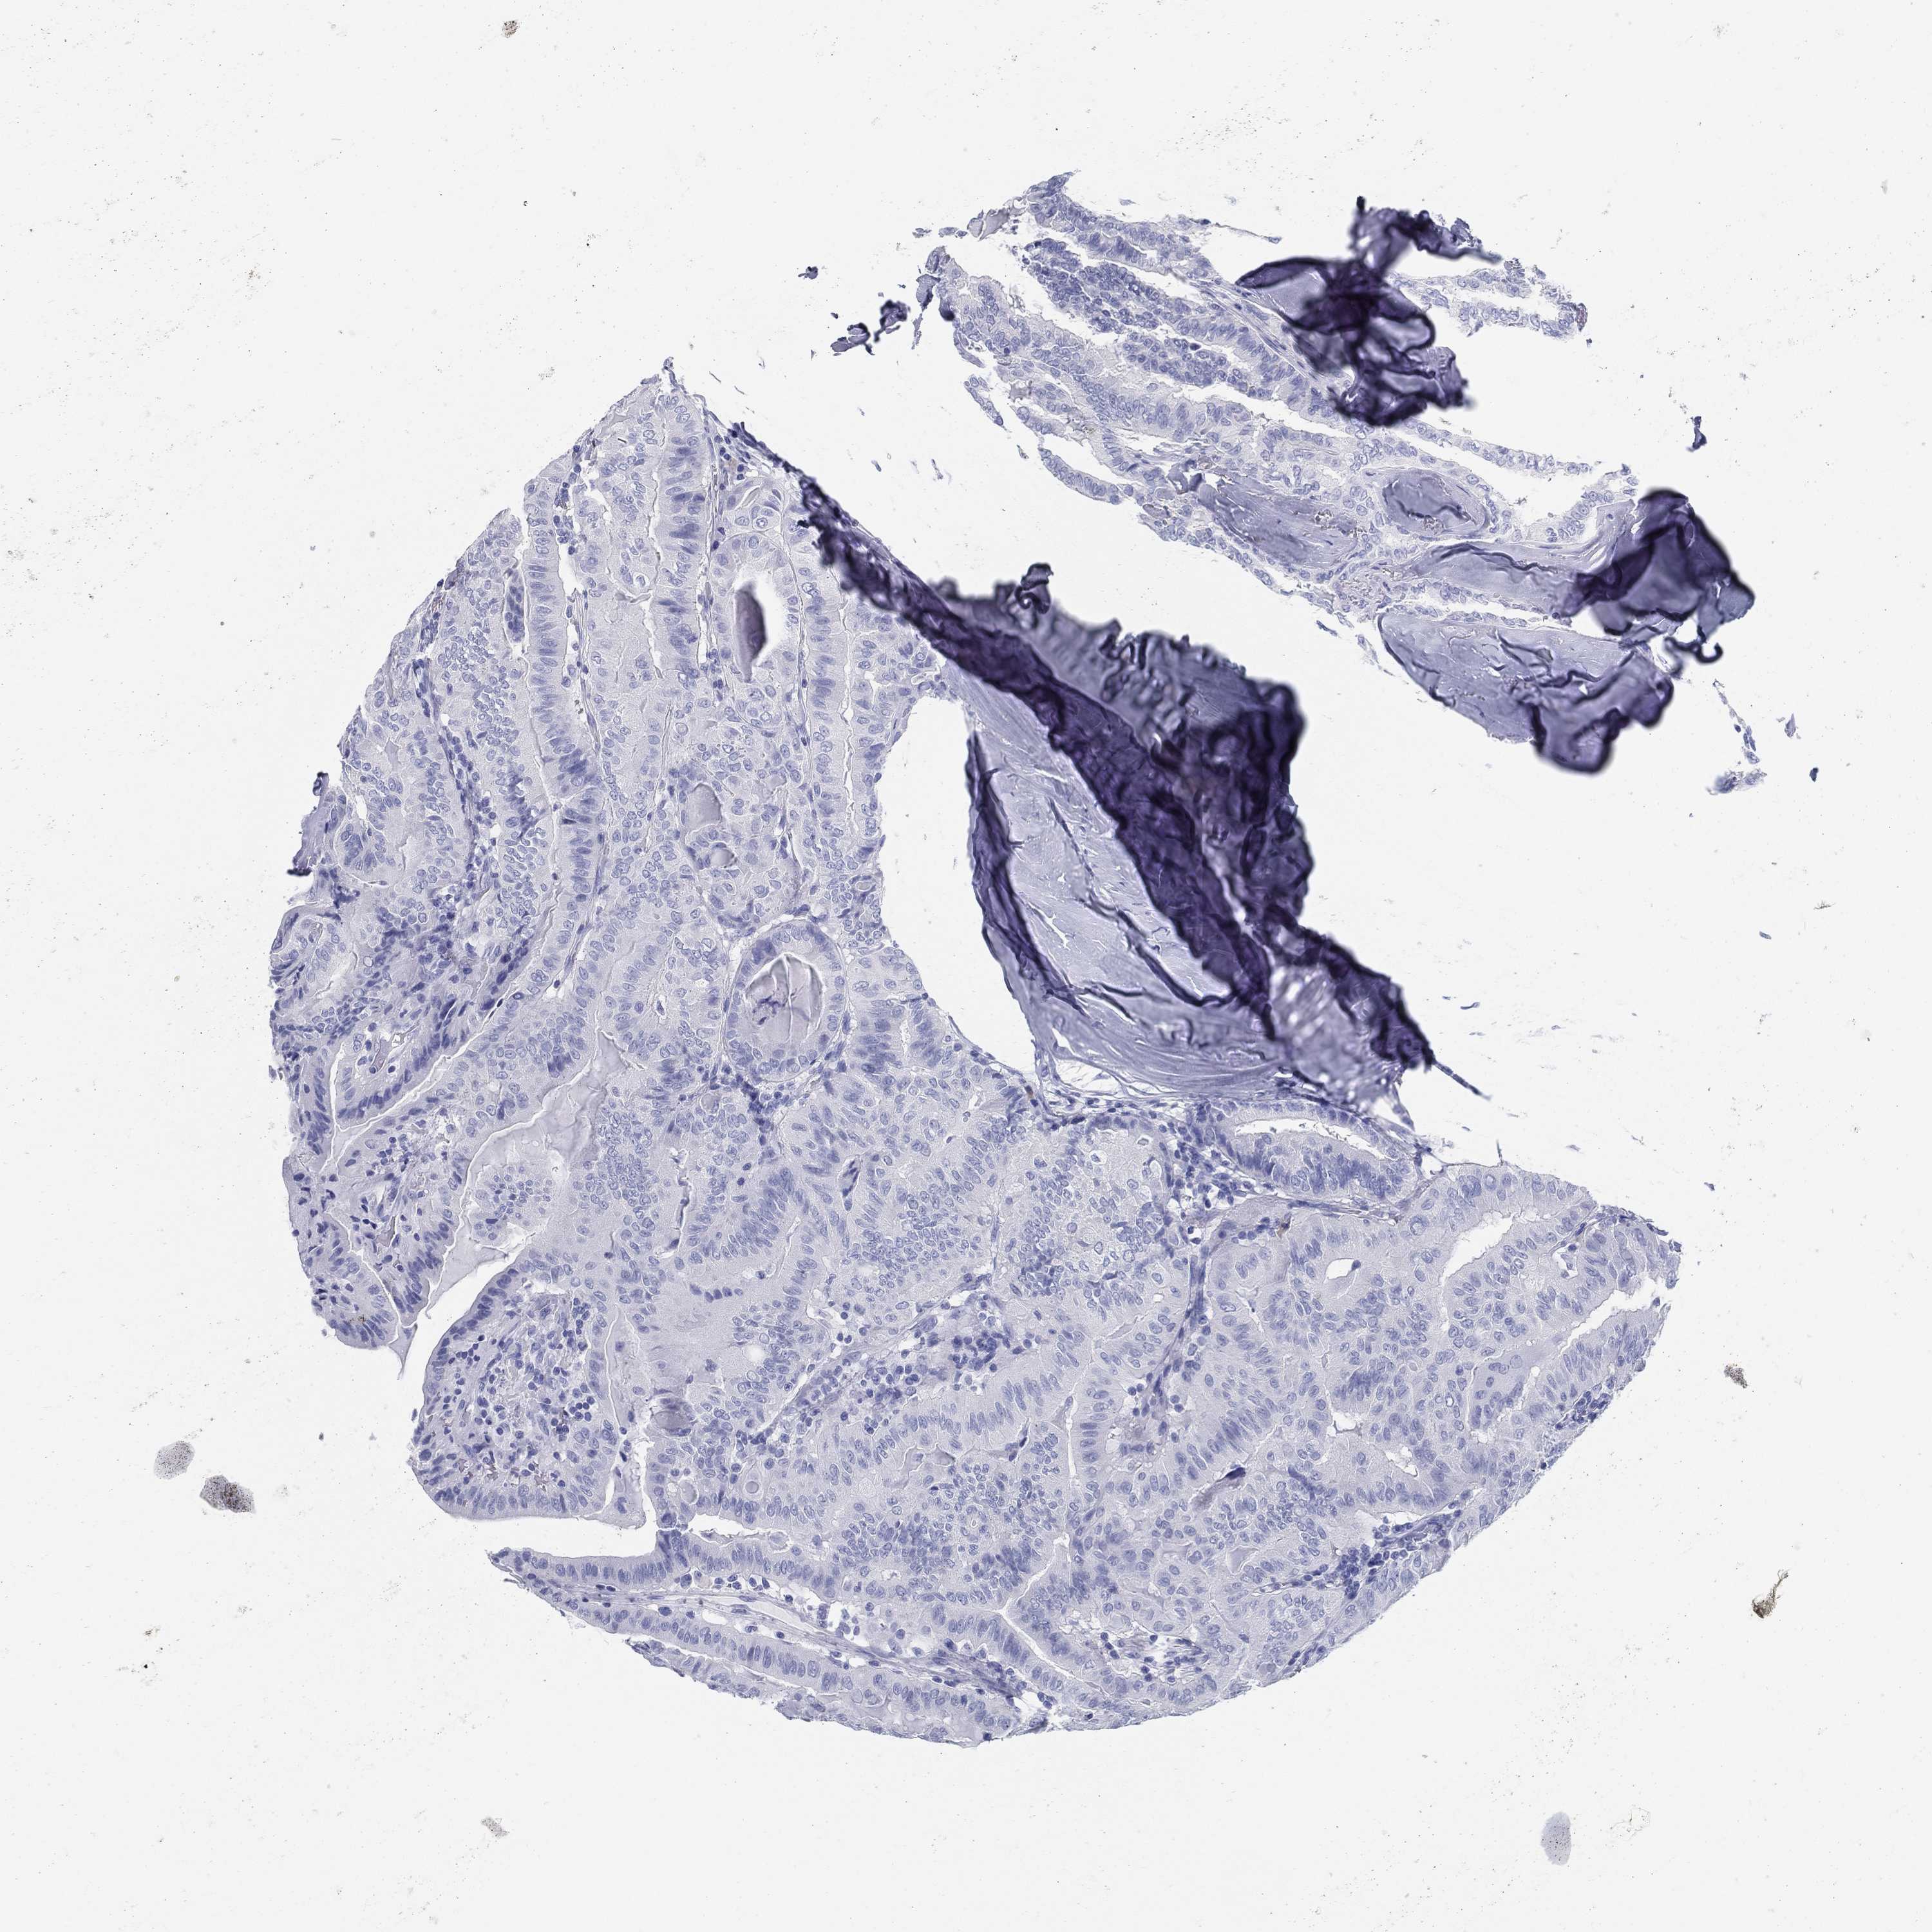

THYROID CANCER - Protein expressioni

A mouse-over function shows sample information and annotation data. Click on an image to view it in a full screen mode. Samples can be filtered based on level of antibody staining by selecting one or several of the following categories: high, medium, low and not detected. The assay and annotation is described here.

Note that samples used for immunohistochemistry by the Human Protein Atlas do not correspond to samples in the TCGA dataset.

Antibody stainingi

Antibody staining in the annotated cell types in the current human tissue is reported as not detected, low, medium, or high, based on conventional immunohistochemistry profiling in selected tissues. This score is based on the combination of the staining intensity and fraction of stained cells.

Each image is clickable and will lead to virtual microscopy that enables deeper exploration of all samples and also displays staining intensity scores, fraction scores and subcellular localization as well as patient and tissue information for each sample.

Antibody HPA079457

Staining

High

Medium

Low

Not detected

Intensity

Strong

Moderate

Weak

Negative

Quantity

>75%

75%-25%

<25%

None

Location

Nuclear

Cytoplasmic/membranous

Cytoplasmic/membranous,nuclear

Papillary adenocarcinoma, NOS

Follicular adenoma carcinoma, NOS